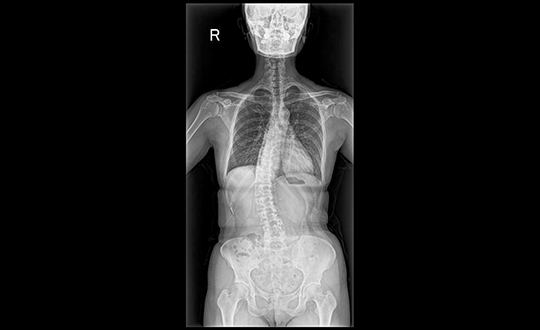

デジタル技術により高画質と低被ばくを両立したレントゲン装置。ISS方式の自動撮影条件設定や長尺撮影に対応し、全脊椎・全下肢の一括撮影も可能。短時間で体への負担が少ない検査を行います。